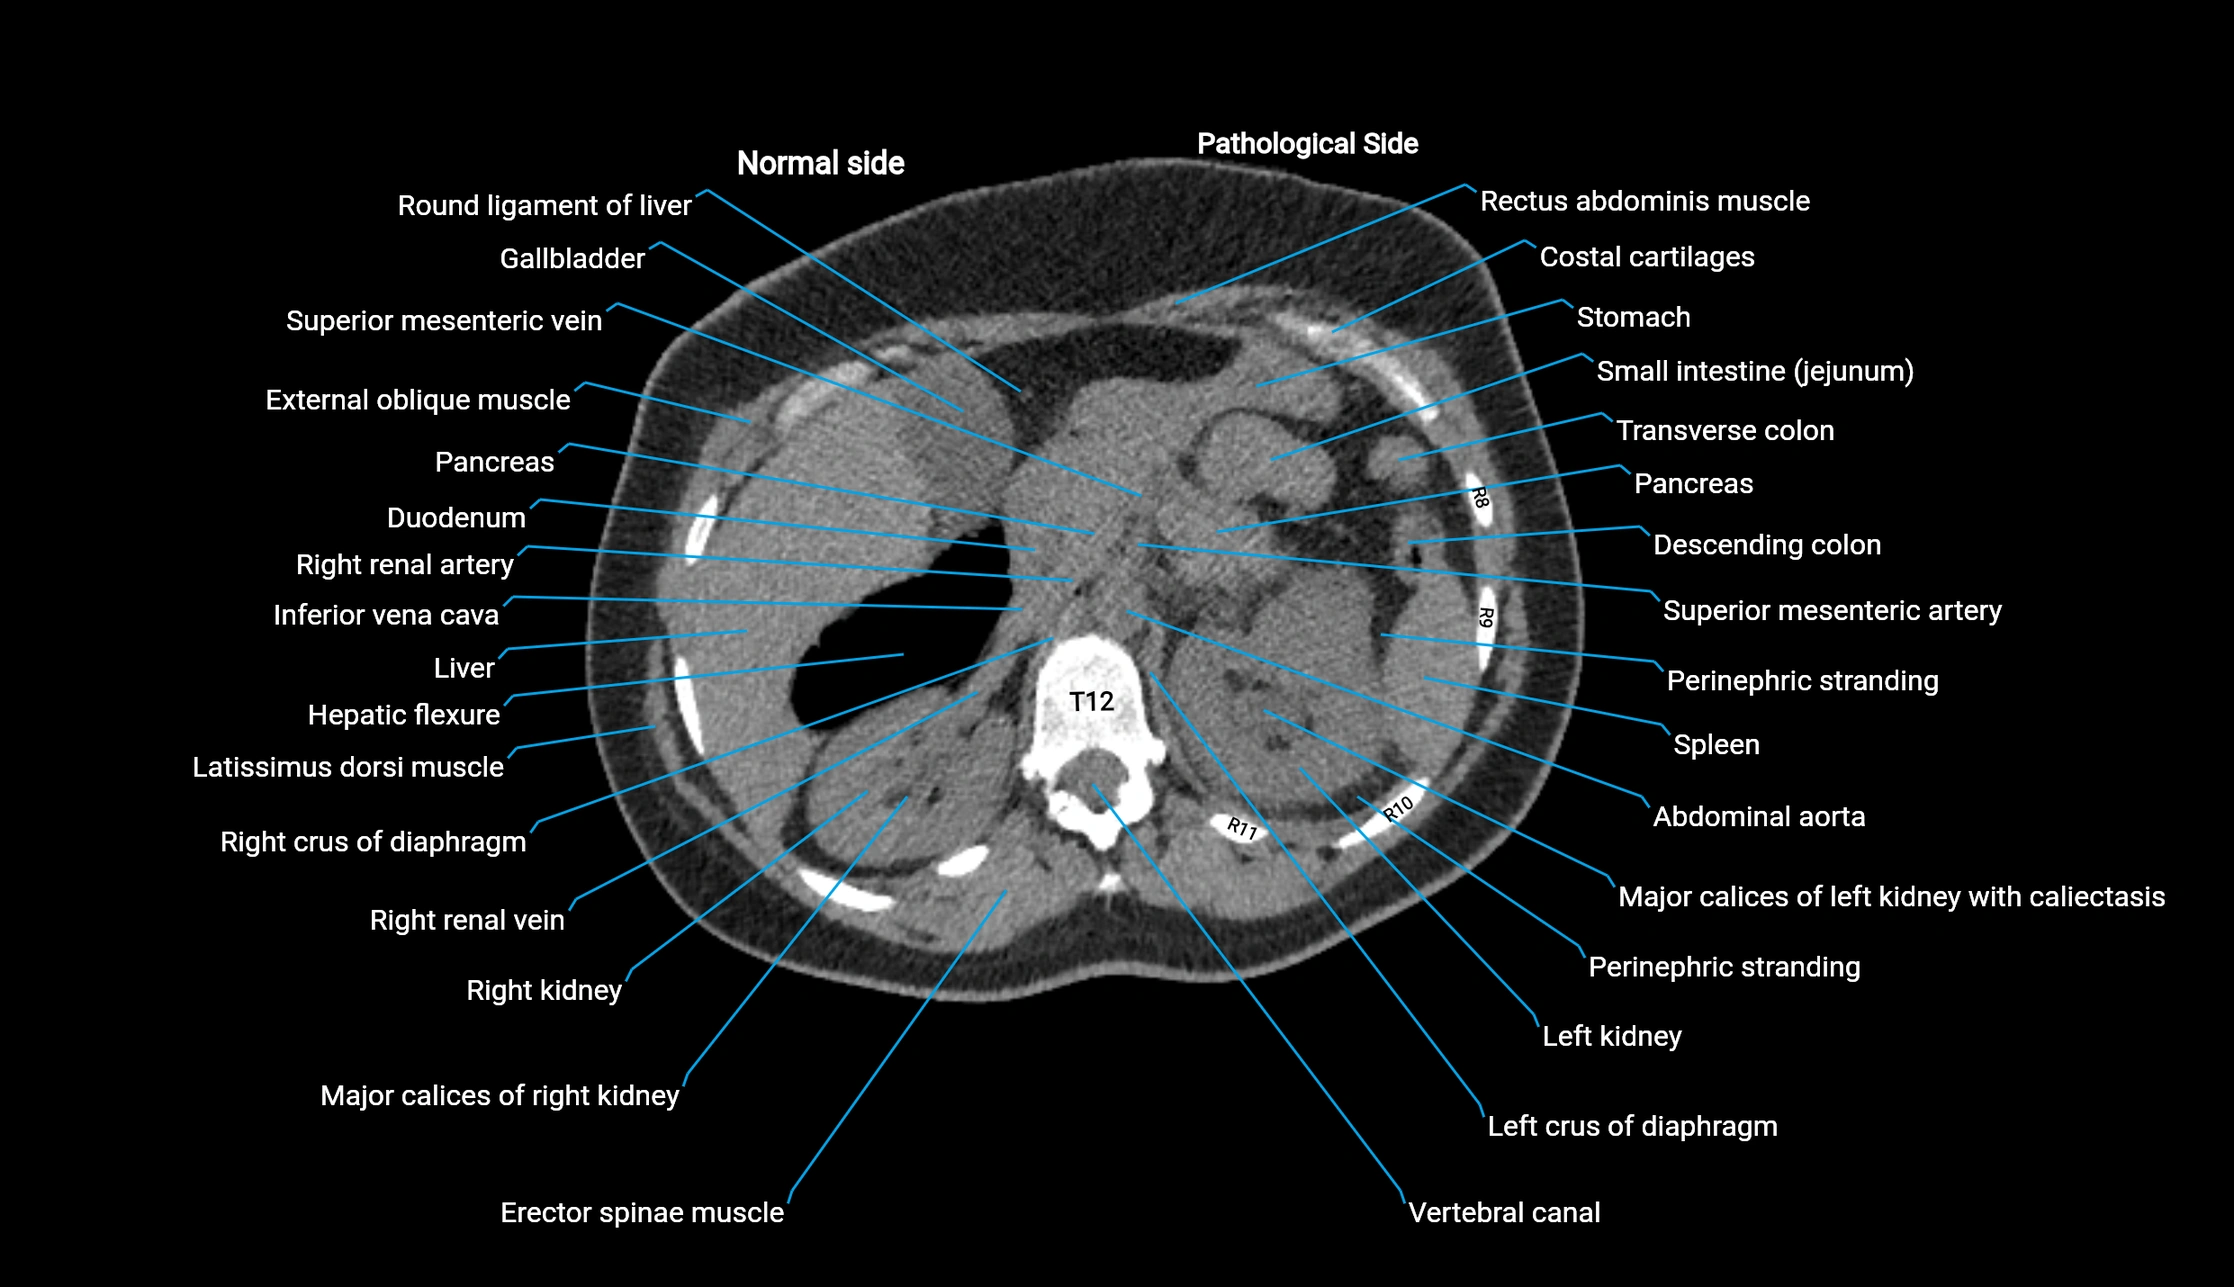

CT image

image